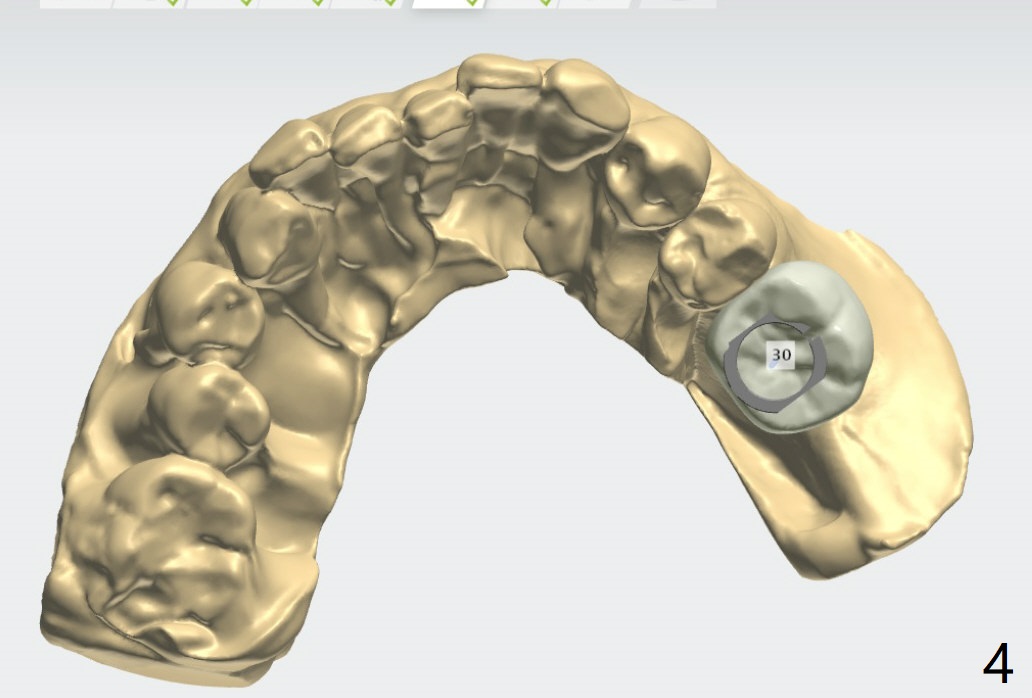

植体

近中牙槽嵴高,植牙后需要profile drill